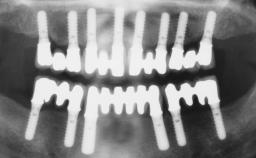

Immediate Loading of Six Implants in the Maxilla and Final Restoration with a Full-Arch Gold/Ceramic FDP Involving the Concept of Tilted Implants

# of Implants 6

Type of Implants One-Piece|Reduced-Diameter

Bone Augmentation Horizontal|Simultaneous

Defining Characteristics Fully edentulous upper jaw to be rehabilitated with four or more implants

Modality Fixed hybrid bridge on 5+ implants

Bone Volume Deficient horizontally, allowing simultaneous augumentation